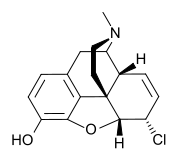

Several semi-synthetic opioids were developed in Germany in the 1910s. The first, oxymorphone, was synthesized from thebaine, an opioid alkaloid in opium poppies, in 1914.[228] Next, Martin Freund and Edmund Speyer developed oxycodone, also from thebaine, at the University of Frankfurt in 1916.[229] In 1920, hydrocodone was prepared by Carl Mannich and Helene Löwenheim, deriving it from codeine. In 1924, hydromorphone was synthesized by adding hydrogen to morphine. Etorphine was synthesized in 1960, from the oripavine in opium poppy straw. Buprenorphine was discovered in 1972.[228]

Opium alkaloids and derivatives

Phenanthrenes naturally occurring in (opium):

Semi-synthetic alkaloid derivatives

Morphinan derivatives

- Butorphanol—agonist/antagonist

- Nalbuphine—agonist/antagonist

- Levorphanol

- Levomethorphan

- Racemethorphan